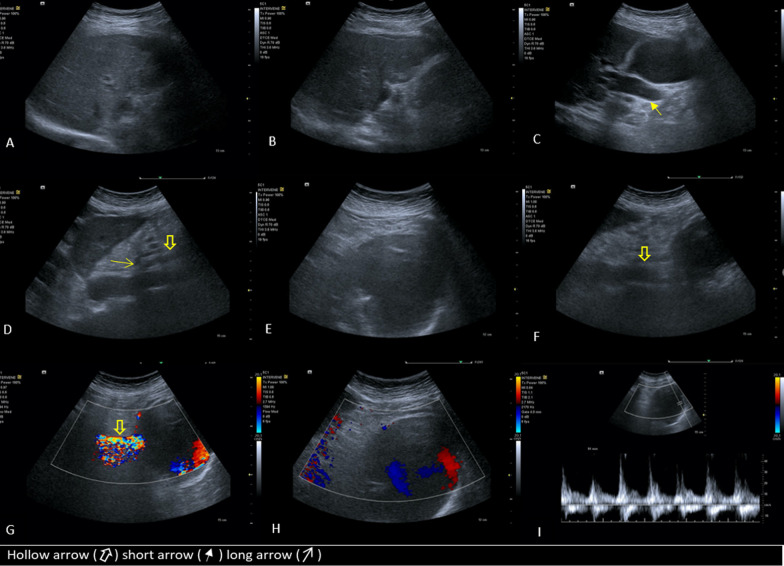

With suspicion of a mass causing obstructive jaundice, ultrasonography was performed. Ultrasonography showed a large cystic mass with peripheral calcification in the head of the pancreas leading to moderate dilation of extra and intrahepatic bile ducts. In the Doppler ultrasound exam, the mass had turbulent blood flow with yin and yang sign and was connected to the superior mesenteric artery, suggesting aneurysmal dilation or pseudoaneurysm of this artery or its branches. Also, the echogenicity of the liver was mildly heterogeneous, and its margin was not completely smooth, in favor of chronic parenchymal liver disease (Fig. 1).

There was mural thrombosis in the aneurysm, which was accompanied by a linear extension of intraluminal contrast through the mural thrombosis, indicating a thrombosis fissuration sign (Fig. 2E). Discontinuous calcification of the aneurysm’s wall was present, and there were areas of focal bulging of the aneurysm’s lumen to the surrounding mesenteric fat, associated with mild stranding and minimal fluid in these areas. Two smaller aneurysms (2.5 × 2.5 cm and 1.5 × 1.2 cm) were also seen adjacent to the superomedial margin of the huge aneurysm, originating from the posterior branch of the gastroduodenal artery (superior posterior pancreaticoduodenal artery) (Figs. 2E, J, 3C, D). A significant narrowing at the origin of the celiac trunk was noted due to diaphragmatic crura compression, indicating median arcuate ligament syndrome (Figs. 1D, 2D, G, 3C).